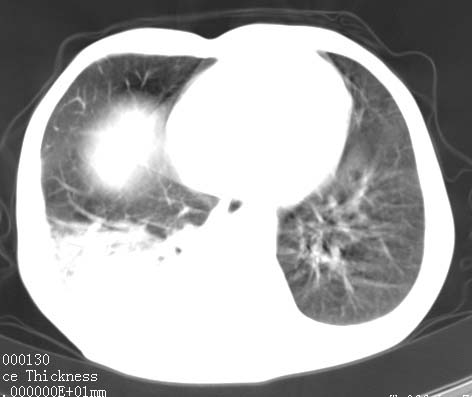

病人女 60岁 咳嗽 气促十余天,大叶性肺炎.

右肺上下叶均见 大片状密度增高影,边界清晰,其内可见支气管充气征,气管支气管通畅。纵膈略向右移位,其内无肿大淋巴结影。首先考虑炎性病变。不排除一些特异性的炎症。不知道发烧吗??wbc高吗??建议治疗后复查!!

看影响还是首先考虑炎性改变,建议实验室检查,还有要警惕炎性肺泡癌,具有的枯枝征象。

右肺感染性病变(大叶性肺炎可能);建议抗炎治疗后复查。

看影像还是首先考虑炎性改变,建议实验室检查,还有要警惕炎性肺泡癌,具有的枯枝征象